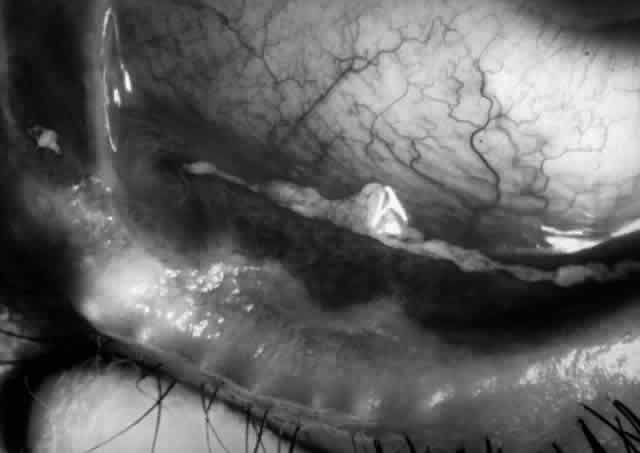

Clinically, the ocular disease in cicatricial pemphigoid (OCP) may present unilaterally in the form of a chronic, recurrent catarrhal conjunctivitis, but it eventually becomes bilateral. Subepithelial fibrosis is characteristic of stage 1 of OCP (Fig. 7). Stage 2 shows fornix foreshortening (Fig. 8), and symblepharon formation is the hallmark of stage 3 (Fig. 9). Stage 4, end-stage disease, is characterized by ankyloblepharon and surface keratinization (Fig. 10). Obstruction of the lacrimal ductules and meibomian gland ducts eventually produces an unstable tear film and progressive sicca syndrome, but it is to be emphasized that OCP is not a dry-eye syndrome until late in the disease course.20 Trichiasis and entropion occur because of the subepithelial fibrosis, with eventual keratopathy, corneal neovascularization, and corneal ulceration and scarring.20

Fig. 7. Stage 1 cicatricial pemphigoid, with cicatrizing conjunctivitis, and fine striae-type areas of subepithelial fibrosis, but without evidence of shrinkage of the conjunctiva.

Fig. 8. Stage 2 cicatricial pemphigoid, with fornix foreshortening and subepithelial fibrosis without frank symblepharon formation.

Fig. 9. Stage 3 of an eye affected by cicatricial pemphigoid. The conjunctival “shrinkage” continued and a frank symblepharon developed.

Fig. 10. Stage 4 cicatricial pemphigoid. Progressive shrinkage of the conjunctiva resulted in extreme trichiasis and distichiasis and keratopathy, with compromise of meibomian ductules and lacrimal ductules and the production of a totally dry eye.